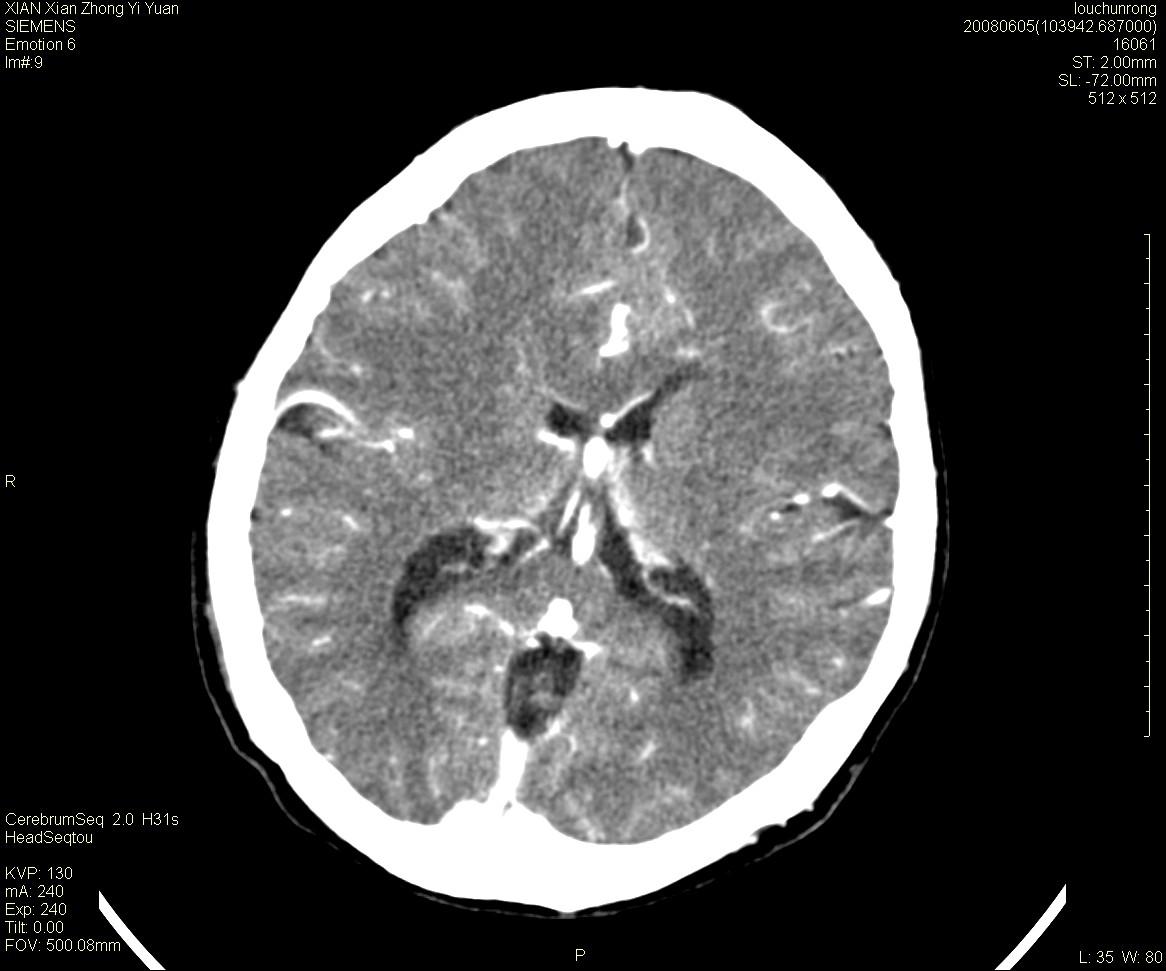

标题: CT13860:F52Y,,头外伤致头晕半天,以前无不适。 [打印本页]

标题: CT13860:F52Y,,头外伤致头晕半天,以前无不适。

层厚2mm。

中线附近、枕叶近枕骨处及脑内多发点条状强化影,考虑血管异常?

先天发育性疾病

大脑大静脉池内的密度不均,双侧脑室增宽,我看右异常这块。战友们看看

侧脑室前角变形、变窄,考虑侧脑室粘合;余未见明显异常。